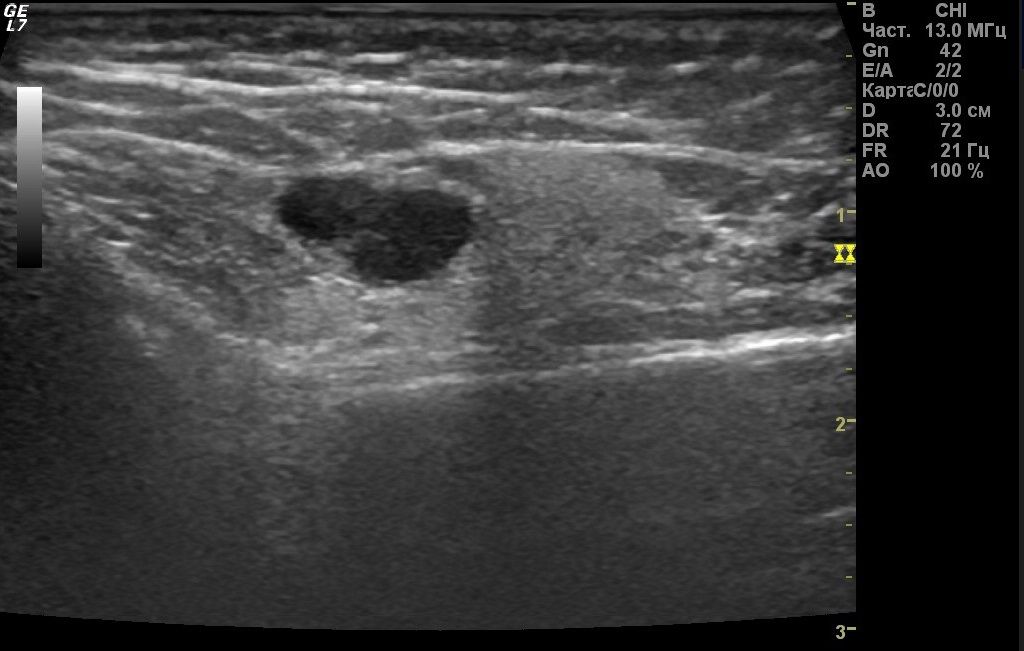

Наиболее эффективным и доступным является УЗИ. Данный метод исследования позволяет выявить в паренхиме железы гиперэхогенные участки, соответствующие воспаленным лимфатическим узлам.